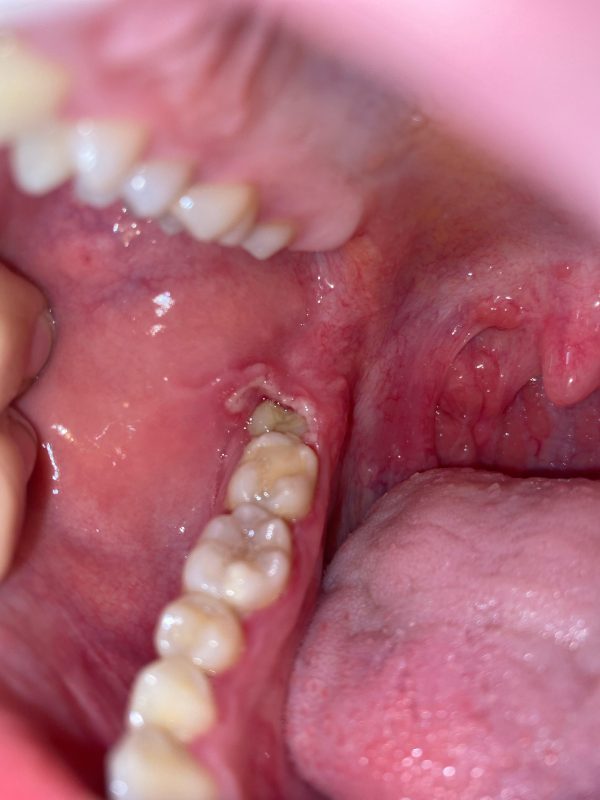

در تجربههای بالینی ما در کلینیک دکتر بیاتی، بیمارانی که برای عفونتهای دندانی مکرر، آمپول دگزامتازون تزریق کردهاند، معمولاً با عفونتهای شدیدتر و درمانهای سختتر وارد میشوند. نتیجه روشن است: دگزامتازون برای عفونت دندان، یک توقف کوتاه است نه درمان. حتی گاهی درد را خاموش میکند، اما عفونت در سکوت پیشرفت میکند.

در کلینیک دکتر بیاتی بارها دیدهایم که تزریق دگزامتازون باعث تأخیر درمان و پیچیدهتر شدن کار شده است. برای دنداندرد، بهترین تصمیم مراجعه سریع به دندانپزشک و برطرفکردن علت است—نه تزریق کورکورانه داروی کورتونی.

دگزامتازون فقط علامت را کاهش میدهد، اما مشکل اصلی همانطور باقی میماند و حتی ممکن است شدیدتر شود. در تجربه بالینی ما در کلینیک دندانپزشکی دکتر بیاتی، بسیاری از بیمارانی که پس از تزریق دگزامتازون احساس “بهبودی کامل” داشتند، چند روز بعد با درد شدیدتر یا عفونت گستردهتر مراجعه کردهاند—چون با خاموش شدن موقت درد، درمان اصلی را به تعویق انداخته بودند.

در تجربه کلینیک دندانپزشکی دکتر بیاتی، بیشترین آسیب زمانی رخ میدهد که فرد تصور میکند درد «درمان» شده و درمان اصلی را به تعویق میاندازد؛ در حالیکه عفونت در حال گسترش است.